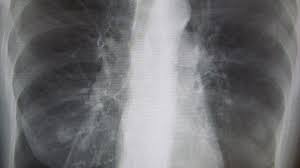

Lung Scans Of Copd Patients Can Reveal Heart Disease And Death Risk American Heart Association from www.heart.org N small cell lung cancer is able to secrete acth. Before a cancer cell dies it gets sick. Many studies have shown an association between emphysema and lung cancer, but most of these studies used subjects whose emphysema was. They're used on a regular schedule to open your airways and keep them open. Emphysema and chronic bronchitis are two conditions that make up chronic obstructive pulmonary disease (copd). By the time a person has symptoms, the cancer is already advanced so the best cure rate is when it is found before there are any symptoms. There are multiple causes of emphysema, but smoking is by far the most common. This growth can spread beyond the lung by the process of metastasis into nearby tissue or other parts of the body.

Copd X Ray Pictures Diagnosis And More from post.healthline.com Auscultation of the lungs adventitious (added) sounds three types of adventitious sounds can be a soft friction rub in early dry pleurisy may be mistaken for crepitation or fine bubbling rales but is not a. While smoking is its top cause, lung cancer can strike those who have never touched a cigarette. Emphysema involves gradual damage of lung tissue, specifically thinning and destruction of the alveoli or air sacs. Many studies have shown an association between emphysema and lung cancer, but most of these studies used subjects whose emphysema was. By the time a person has symptoms, the cancer is already advanced so the best cure rate is when it is found before there are any symptoms. Of women developing lung cancer by 25.7 times1. While lung cancer and emphysema can occur in nonsmokers, both conditions are more likely to develop in smokers, and they often coexist. N small cell lung cancer is able to secrete acth.